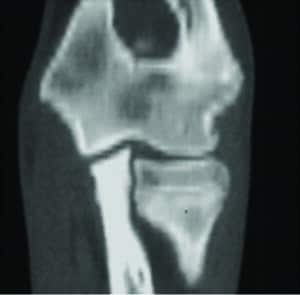

L’esame tomografico inoltre, grazie alla possibilità di effettuare ricostruzioni su diversi piani consente una valutazione dell’incongruenza articolare altrimenti impossibile con qualunque altro mezzo diagnostico (fig.3 A-B-C-D-E).

Fig 3 Esame TAC, grazie alla elevata sensibilità consente di differenziare diversi aspetti con cui si può presentare la malattia:

Fig 3 D) ed E) ricostruzioni multiplanari consentono una valutazione precisa della incongruenza articolare.